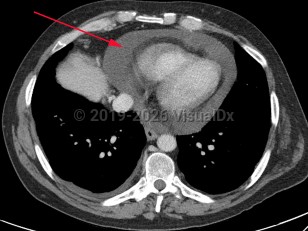

Aortic dissectionAortic dissection

Pericardial effusionPericardial effusion

Cardiac tamponadeCardiac tamponade